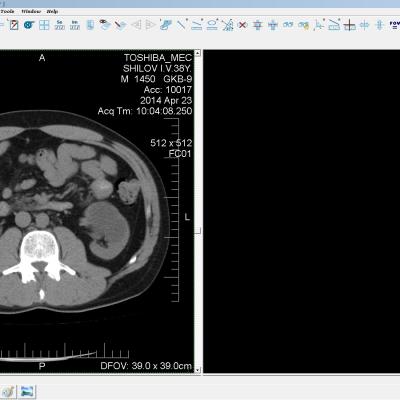

Здравствуйте. У меня киста левой почки. Из заключения: левая почка увеличена, деформирована за счёт наличия в среднем сегменте округлого жидкостного +6, +15 HU образования 66х53 мм, деформирует, поддавливает чаше-лоханочную систему. Сосудистые ножки структурные. В урологии мне сперва предложили лапароскопию, когда я лёг на операцию - изменили на полостную в связи со сложностью. Потом сказали что шансов вырезать кисту без почки практически нет. Даже если кисту удалить чудесным способом, то почка всё равно сложится и не будет работать. В итоге операцию отменили. Скажите, пожалуйста, есть ли современный метод удалить кисту и сохранить почку в моём случае? Томография почки в приложениях. Заранее благодарю.

Эту кисту можно просто пропунктировать, аспирировать и склерозировать - под местной анестезией. Ничего сверхестетственного не определяется по данным КТ. Можете написать мне на почту. aristova-tatyana@mail.ru